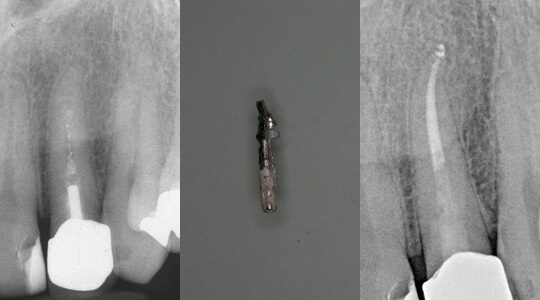

Bild links: Oberer Backenzahn mit abgebrochenem Instrument in der vorderen-äußeren Wurzel.

Bild rechts: Nach Entfernung des Instrumentenfragmentes ist die Instrumentierung und Reinigung des Wurzelkanals möglich (Röntgenkontrastaufnahme).